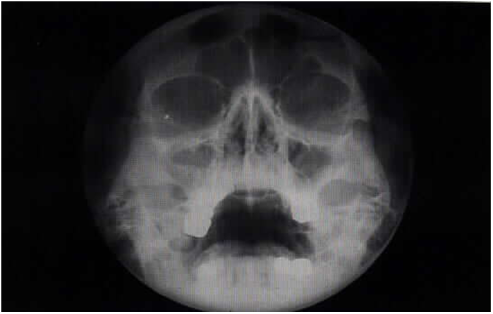

Дегенерация синуса

Дегенерация синуса 83 фото